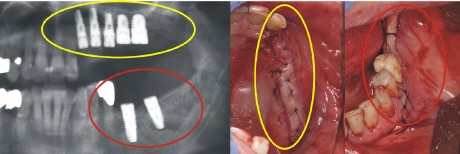

Implantation

Im Oberkiefer (gelber Kreis) und im Unterkiefer (roter Kreis) wurden die fehlenden Zähne durch Implantate ersetzt. Auf den rechten Bildern sieht man, dass die Zähne geschlossen, also geschützt unter der Schleimhaut, einheilen.